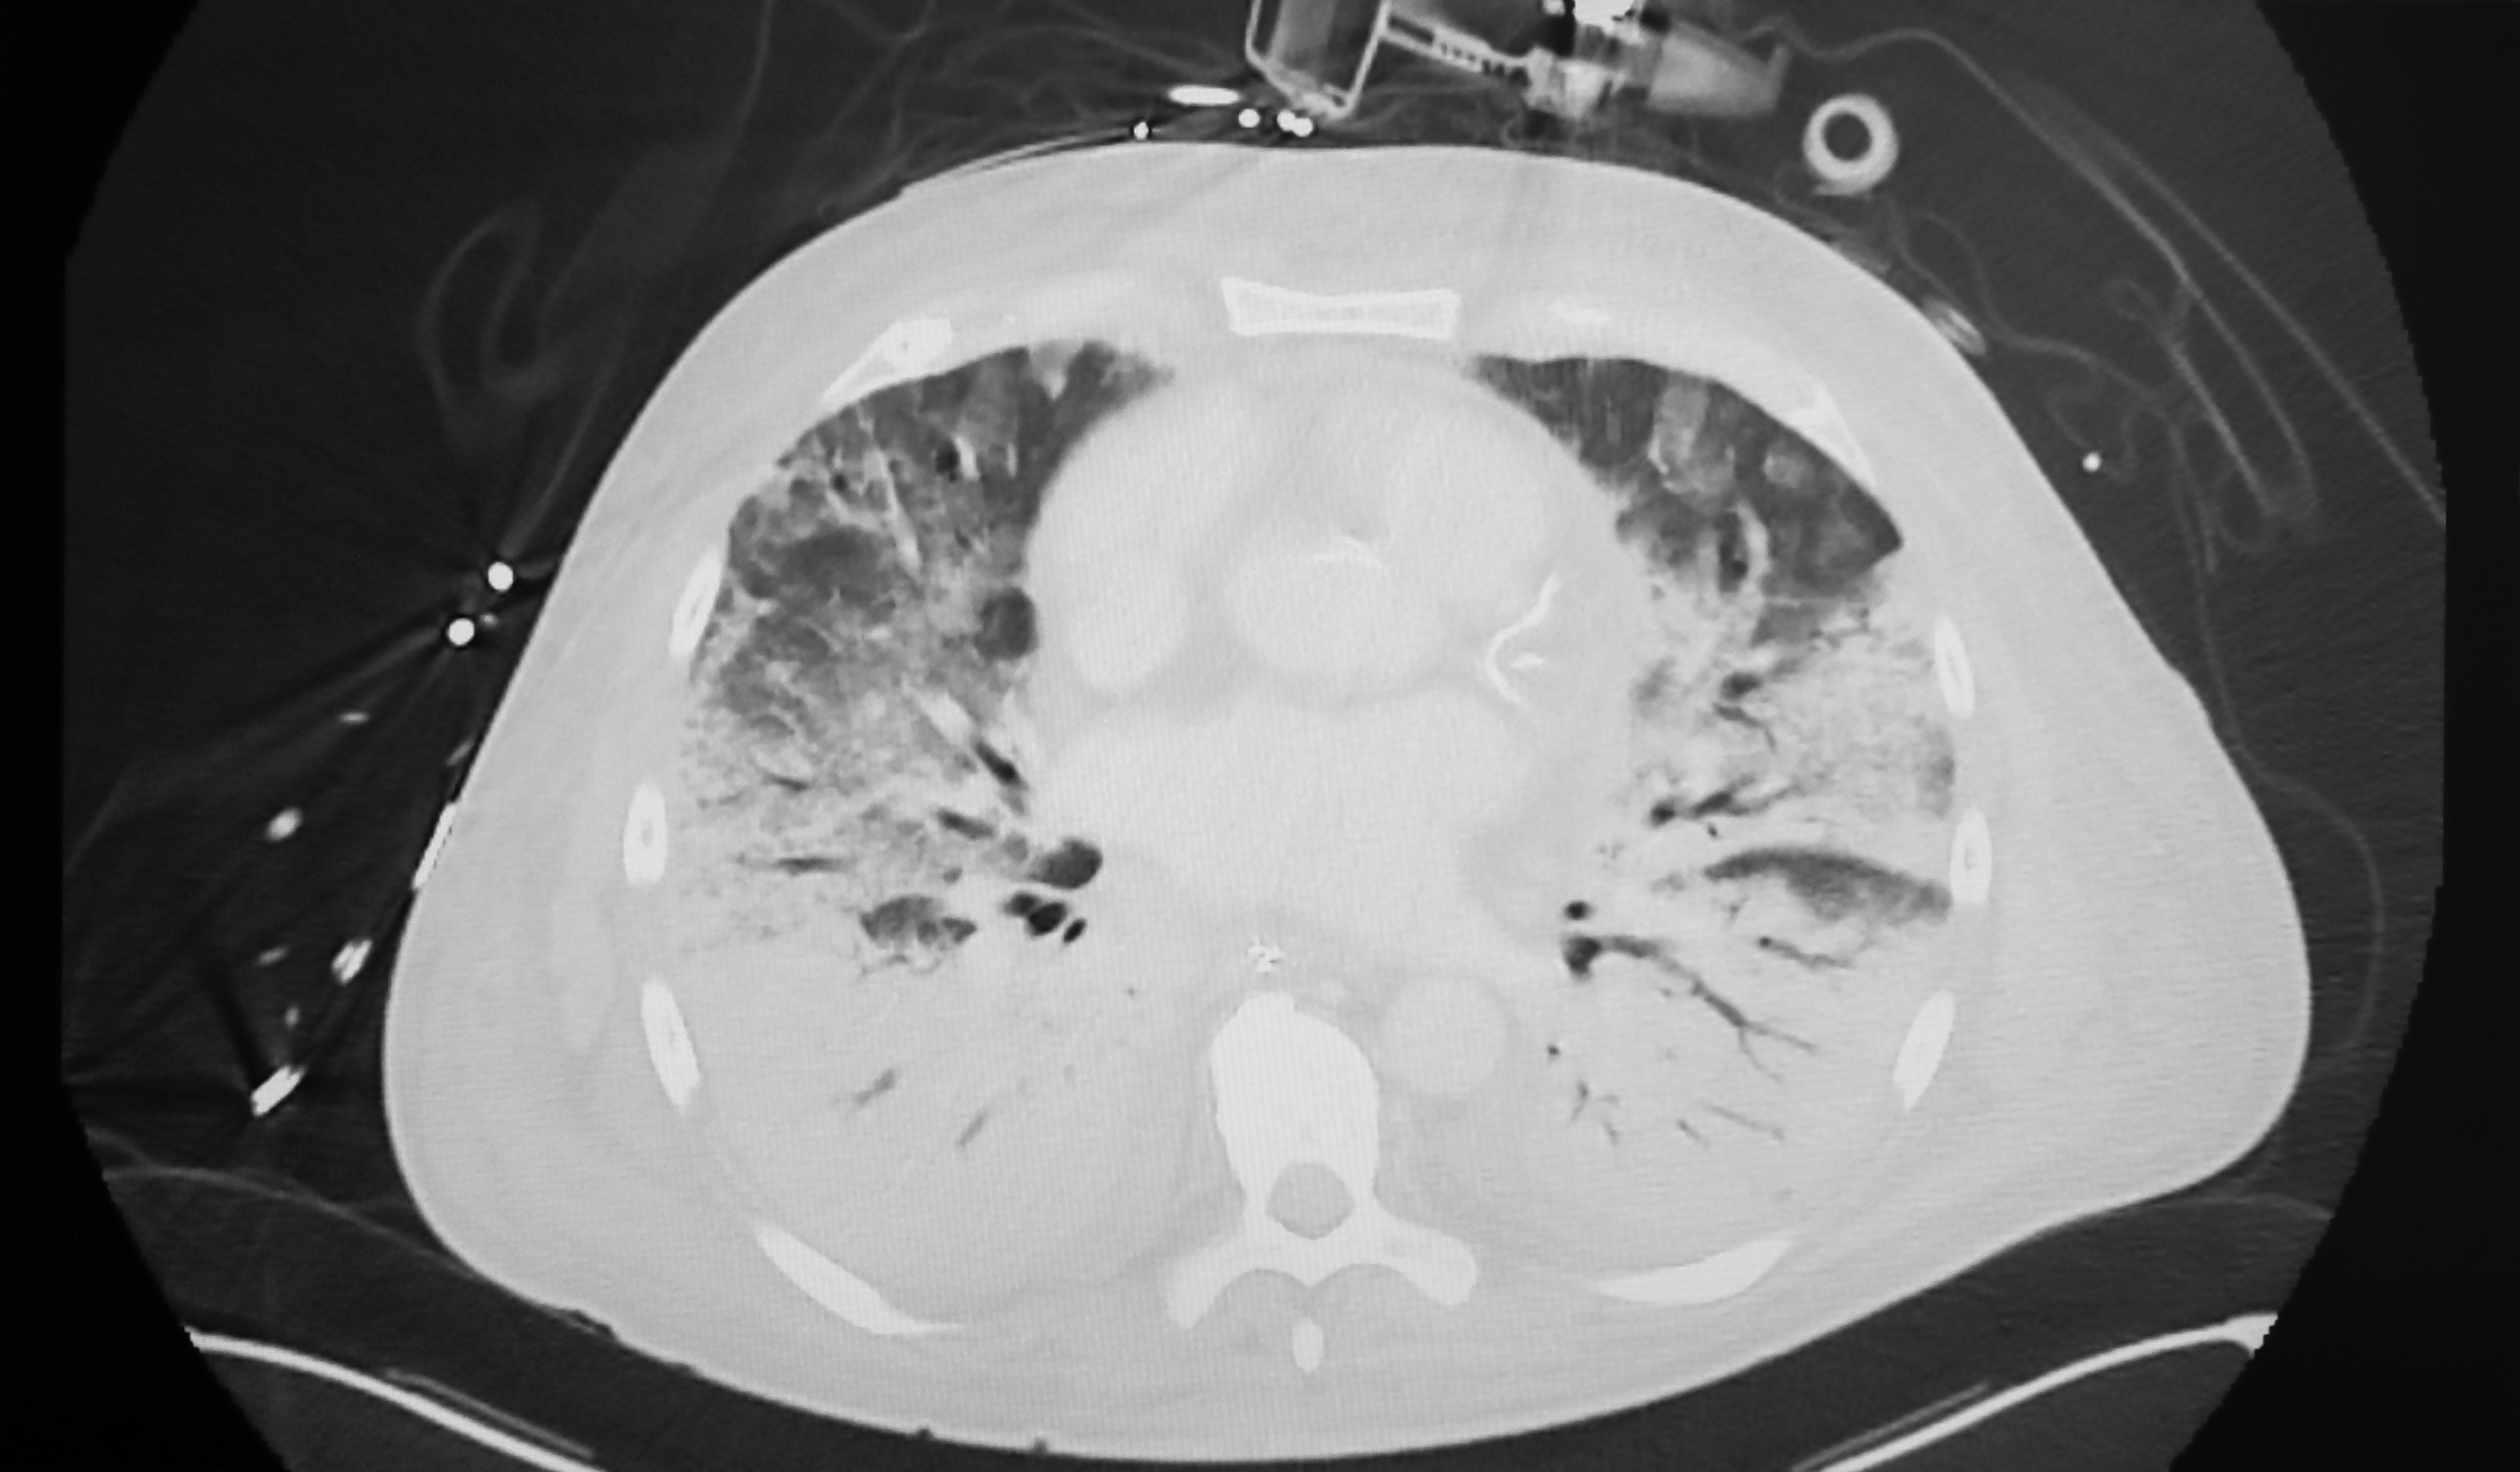

An expert panel broadened the definition of acute respiratory distress syndrome (ARDS).

They announced this at the American Thoracic Society meeting in May 2023. Thirty-two experts virtually to update the 2012 update (in Berlin), and declared that ARDS shall henceforth include anyone with:

PaO2/FiO2 ≤300 mmHg (on an arterial blood gas) or

SpO2/FiO2 ≤315m…